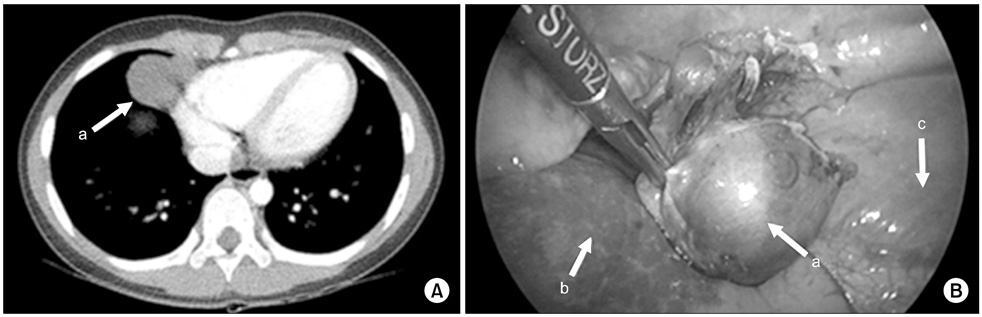

Venous malformation. (A) There was mass at cardoiphrenic angle and it was suspected an inflammatory pseudo-tumor or congenital lung lesion like cystic lymphangioma on chest CT (3.0×3.6×2.3-cm-sized mass). (B) It was being originated from right pleura and was resected clearly. Arrows: a, mass; b, lung; c, diaphragm.

Fig. 7 Venous malformation. (A) There was mass at cardoiphrenic angle and it was suspected an inflammatory pseudo-tumor or congenital lung lesion like cystic lymphangioma on chest CT (3.0×3.6×2.3-cm-sized mass). (B) It was being originated from right pleura and was resected clearly. Arrows: a, mass; b, lung; c, diaphragm.